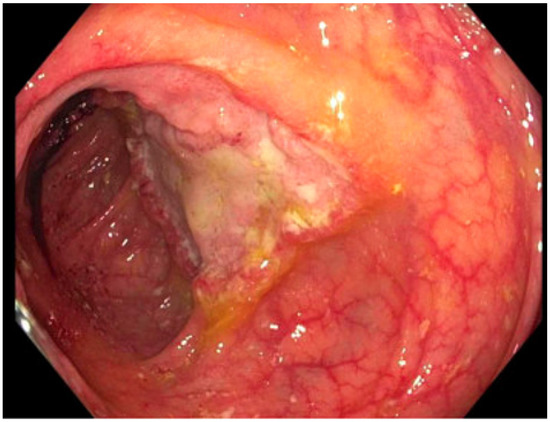

| 3: Histoplasmosis | 38 YO, 14 years post transplant. Symptoms of low-grade fever and weight loss prompted colonoscopy. | CT chest/abdomen/pelvis: bowel wall thickening, lymphadenopathy, no acute pulmonary changes. Colonoscopy biopsy: Histoplasma (Figure 2). Histoplasma blood antibody: negative. Histoplasma urine antigen: 7.01 ng/mL. | Liposomal amphotericin 5 mg/kg for 7 days, then step-down to itraconazole 200 mg TID for 9 doses, followed by 200 mg BID Itraconazole trough 1.5 mcg/mL. | Remains on itraconazole after two years without significant side effects. Colonic thickening resolved five months after treatment initiation. Histoplasma urine antigen decreased to 0.77 ng/mL after 8 weeks of treatment. |